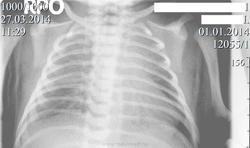

Новорождённый.  Направлен с подозрением на врождённый порок  сердца.R-графия  лёгких  в прямой проекции.

Возникли вопросы по оценке  тяжистой тени слева на фоне тени сердца и справа в среднем поле.

Я не сосем понял, что это было, но  на контрольных R-граммах сегодня ( представленный снимок выполнен вчера и были назначены снимки в  прямой, левой и правой боковых проекциях) нашёл  только нитевидное  уплотнение малой междолевой плевры справа.

Уважаемый коллега! Ну точно ни Х.орошо ничего не видно. Одно видно- легкие воздушны, сердце на месте и без оказий. Остальное в процессе.smiley Т.е. динамика решает тут все.

Не факт, что с первым вдохом легкие расправляются на сто процентов.

Тень слева, очевидно, была экстракорпоральной, если на контрольном снимке ее нету. Может что-то забыли под младенцем. Справа, с учетом динамики, небольшой выпот в междолевой плевре.

R-грамммы в боковых прокциях были сразу назначены и на следующий день выполнены, только я на них ничего не увидел, кроме уплотнения междолевой плевры справа по малой и главной щели в базальном отделе.

Может быть, но она скорее эта  тень производила впечатение анатомического образования-  возможно, какого-то сосуда( только какого?).